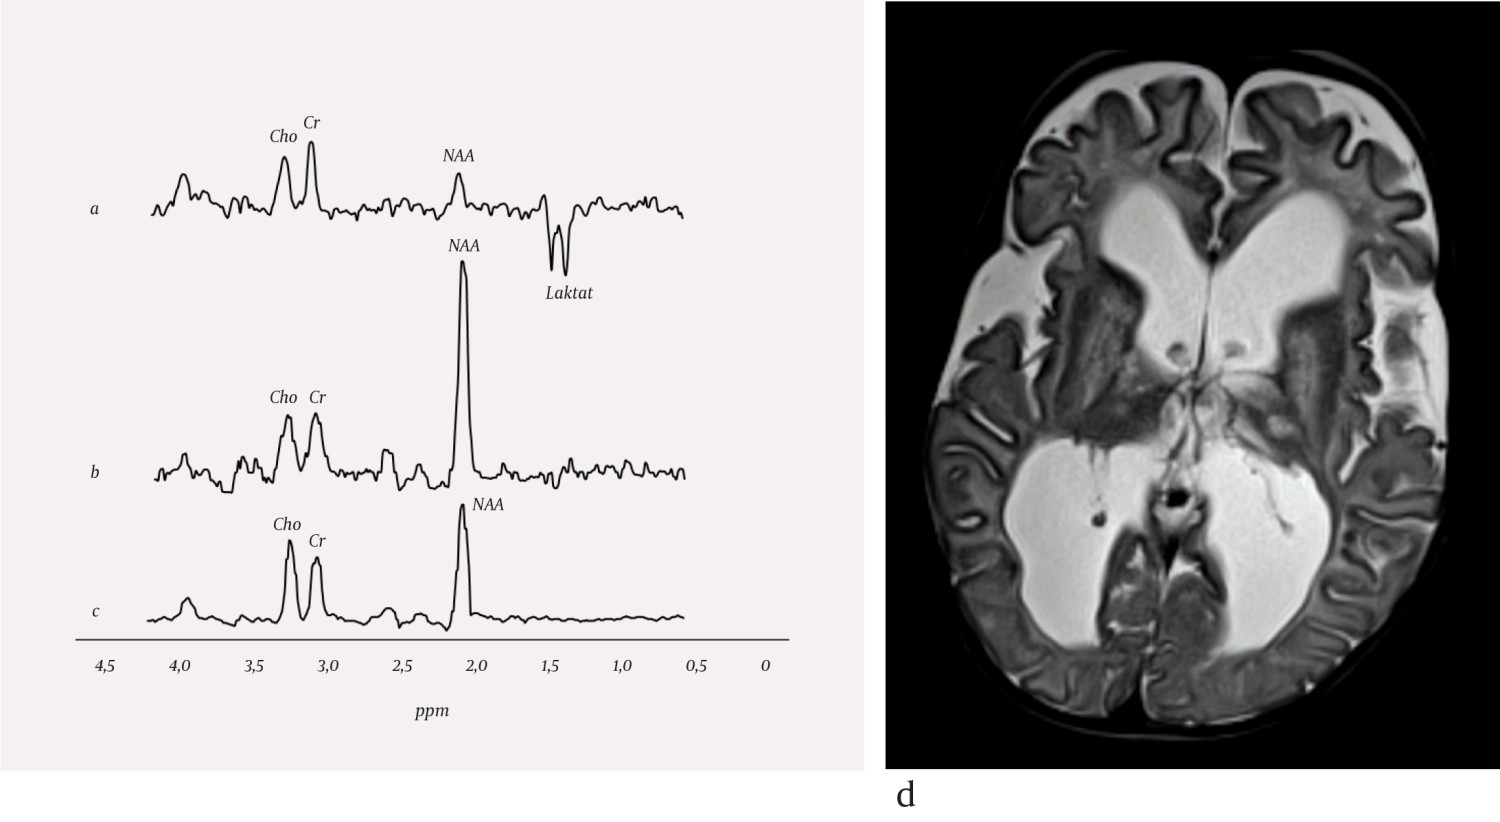

Nevrometabolske sykdommer utgjør en stor og heterogen gruppe medfødte tilstander. Insidens for disse tilstandene enkeltvis er svært lav, mens samlet insidens er estimert til å være 1 per 800–2 500 fødsler (3, 4). De fleste pasienter med nevrometabolsk sykdom har forsinket utvikling eller nevrologiske symptomer og tegn som nyfødt eller i tidlig barnealder. Unntaksvis kan nevrometabolske sykdommer også debutere i voksen alder. Mange nevrometabolske sykdommer gir uspesifikke strukturelle forandringer i sentralnervesystemet som kan karakteriseres med MR-avbildning, men det kan være vanskelig å stille en sikker diagnose kun fra bildefunn. For enkelte nevrometabolske tilstander kan derfor MR-spektroskopi være nyttig på grunn av evnen til å beskrive hjernevevets sammensetning av metabolitter. Noen få sykdommer har en helt sykdomsspesifikk profil ved MR-spektroskopi (5), mens andre har en MR-spektroskopi-profil som kombinert med bildefunn og resultater av kliniske undersøkelser er spesifikk for tilstanden (2). Vanlige endringer i patologiske MR-spektre er redusert mengde N-acetylaspartat, redusert eller økt mengde kolin, økt mengde myo-inositol og tilstedeværelse av laktat. Eksempler på nevrometabolske sykdommer som MR-spektroskopi kan bidra til å karakterisere, er mitokondrielle sykdommer og enzymatiske defekter (figur 1a og 1b).

Enzymatiske defekter kan medføre svikt i cellulære prosesser dersom et spesifikt enzym mangler eller er defekt. Alvorlighetsgrad avhenger av hvilket enzym som er defekt, og det kliniske bildet ved sykdommer i denne gruppen er høyst varierende. Canavans sykdom er en leukodystrofi, hvor hvit substans blir ødematøs, og det dannes væskefylte hulrom (figur 1d). Pasienter med Canavans sykdom har spesifikke genmutasjoner som medfører mangel på enzymet aspartoacylase, som er essensielt for spalting av N-acetylaspartat til aspartat og acetat. Enzymmangelen medfører opphoping av N-acetylaspartat i hjernen og hindret syntese av myelin. Den vanligste formen av sykdommen opptrer ved seks måneders alder og gir omfattende svikt i nevrologiske funksjoner (6). Sykdomstegn er irritabilitet, hypotoni og dårlig overkroppskontroll. Sykdommen medfører sterkt redusert utvikling hos barnet, og kan gi økt hodeomkrets, dårlig øyemotorikk, blindhet, epilepsi, muskelstivhet og spasmer. Forventet levetid er omkring ti år. MR-spektroskopi av pasienter med Canavans sykdom viser sterkt forhøyet signal fra N-acetylaspartat (figur 1b). Canavans sykdom er eneste kjente metabolske sykdom som medfører en økning i mengde av N-acetylaspartat.

Mitokondriesykdommer er en heterogen sykdomsgruppe som gir progressiv eller intermitterende hjerneskade (7). MR-avbildning viser varierende funn med ødem og vevsdestruksjon, men bilateral affeksjon av basalgangliene er typisk. Sammen med MR-avbildning og kliniske funn kan MR-spektroskopi bidra til å identifisere og karakterisere mitokondrielle sykdommer. Det mest gjennomgående funnet ved MR-spektroskopi er tilstedeværelse av laktat på grunn av endret intracellulær energiproduksjon, ofte fulgt av redusert N-acetylaspartat, som indikerer celletap. Leighs syndrom er en mitokondriopati som kan gi utviklingsforsinkelse, spastisitet og hjernestammedysfunksjon. MR-avbildning viser typisk symmetriske signalforandringer i basalgangliene, thalamus og hjernestammen. Laktat i MR-spektre fra disse områdene styrker mistanken om Leighs syndrom (figur 1a).